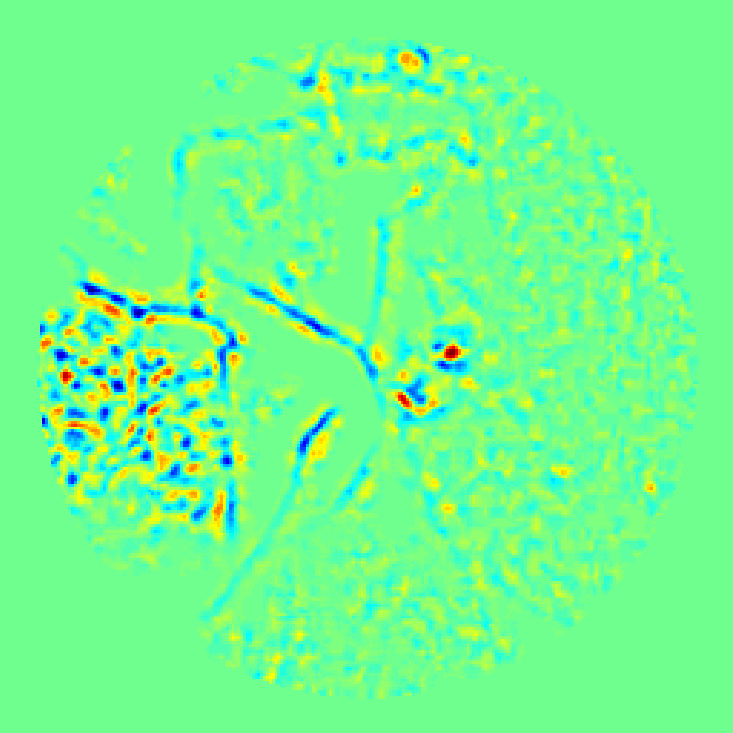

In Figure 1 (g) we show the result of mid-pass filtering . We observe several features present in with the most prominent one corresponding to a polyp. To perform the binary classification we need to assign a numerical quantity to each of these features that would determine how likely does each of them correspond to a polyp.

An example of a binary segmentation obtained with (10) is shown in Figure 1 (h), where four features can be seen. By features we mean the connected components of , which can be found using an algorithm by Haralick and Shapiro [14]. It provides a decomposition

Decomposition (12) is illustrated in Figure 1 (h), where the four features are numbered in the order they are found by the algorithm.